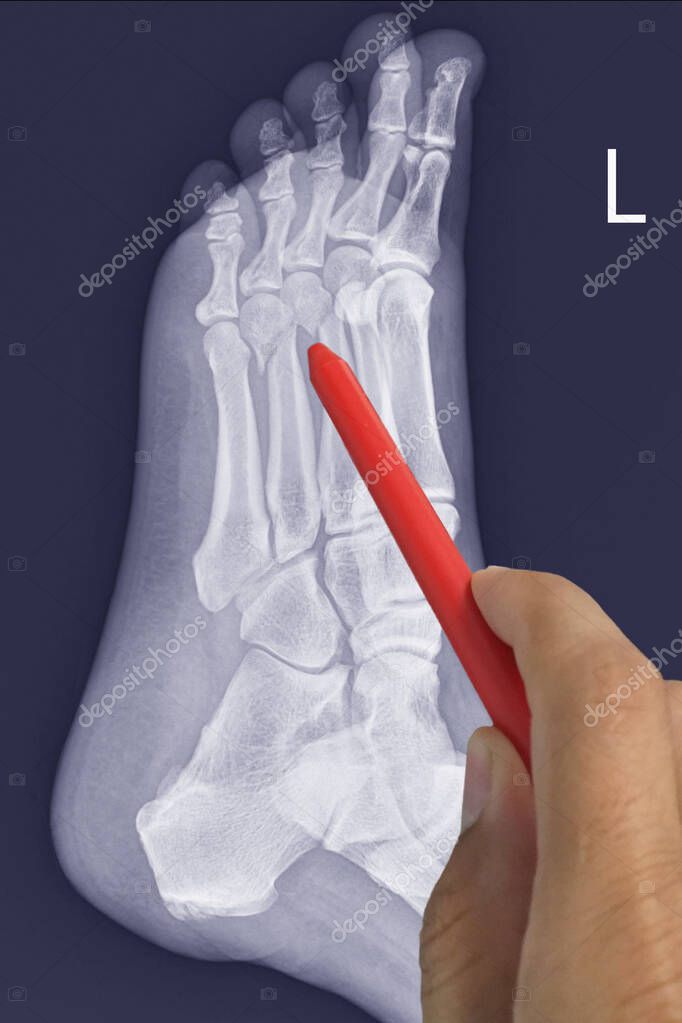

Una radiografía de una fractura de hueso metatarsiano humano Foto Premium Quinto Hueso Metatarsiano Roto Se explica cómo se diagnostica, cómo se trata y cómo se previene esta fractura, con ejemplos de casos famosos y consejos del dr. Esta fractura, ubicada en el hueso del. La fractura del quinto metatarsiano es una lesión común en deportistas y personas activas. La fractura del 5º metatarsiano del pie es una lesión común entre los deportistas, que suele. Quinto Hueso Metatarsiano Roto.

Una radiografía de una fractura de hueso metatarsiano humano Foto Premium Quinto Hueso Metatarsiano Roto En este artículo vamos a hablar sobre la recuperación de fractura de base del 5º metatarsiano, también conocida como fractura de jones. Estos son algunos ejemplos de ejercicios que usted puede probar. Aprende cómo se clasifica, se trata y se recupera la fractura de los metatarsianos del pie, según el número, el desplazamiento y la localización de los huesos afectados.. Quinto Hueso Metatarsiano Roto.